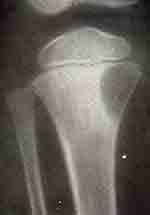

О расположении остеобластокластом у детей данных в литературе мы не нашли. Структура очага остеобластокластомы зависит от формы опухоли. При литической форме она более или менее однородна с отсутствием вкраплений костной ткани в тени опухоли, а при кистозных формах — ячеисто-трабекулярная.

В случае прорыва литической остеобластокластомы за пределы надкостницы она может иметь костный козырек (прерывистые периостальные наслоения), который имитирует остеогенную саркому.